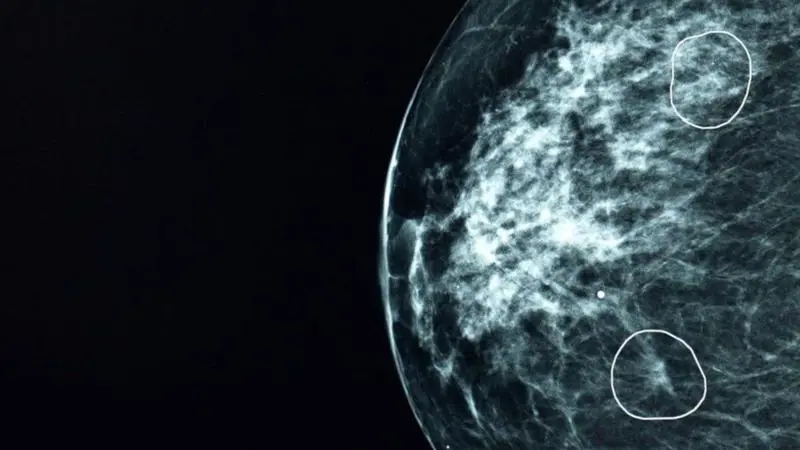

د. چنارعەلی بەرپرسی کۆنترۆڵی شێرپەنجە لە وەزارەتی تەندروستی حکومەتی هەرێمی، لە کۆنفرانسێکی رۆژنامەوانیدا رایگەیاند، تائێستا 71 هەزار و 74 تووشبووی شێرپەنجە لە هەرێمی کوردستان تۆمار کراون، تەنیا لە ساڵی 2022دا نۆ هەزار و 61 تووشبووی شێرپەنجە تۆمارکراون، کە زۆرترینیان لە هەولێرن لە دوای هەولێر، پارێزگای سلێمانی بە پلەی دووەم و دهۆکیش بە پلەی سێیەم لە رێژەی تووشبووانی شێرپەنجە.

ئاماژەی بەوەشکرد، 10 جۆر شێرپەنجە لە هەرێمی کوردستان بڵاوبوونەتەوە، باوترین جۆریان شێرپەنجەی مەمکە و دواتریش شێرپەنجەی کۆڵۆن.